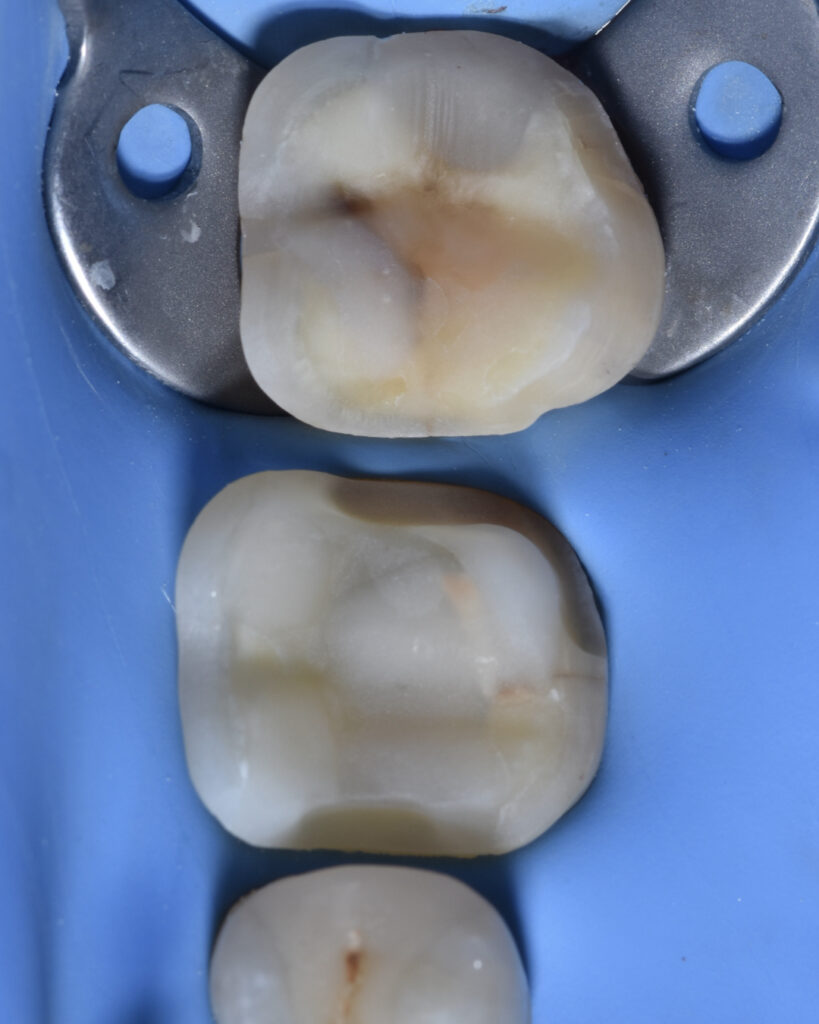

Tooth 3.6 was severely compromised and was managed with endodontic treatment, deep margin elevation, and an indirect adhesive restoration with full cuspal coverage using a lithium disilicate overlay.

Tooth 3.7 presented a large MOD carious lesion, with both distal cusps and the mesiolingual cusp structurally compromised.

The prosthetic restorations were treated as follows:

• 9% hydrofluoric acid for 10 seconds

• 37% orthophosphoric acid for 90 seconds

• Silane application

• Universal adhesive

Adhesive cementation was performed using preheated composite resin.